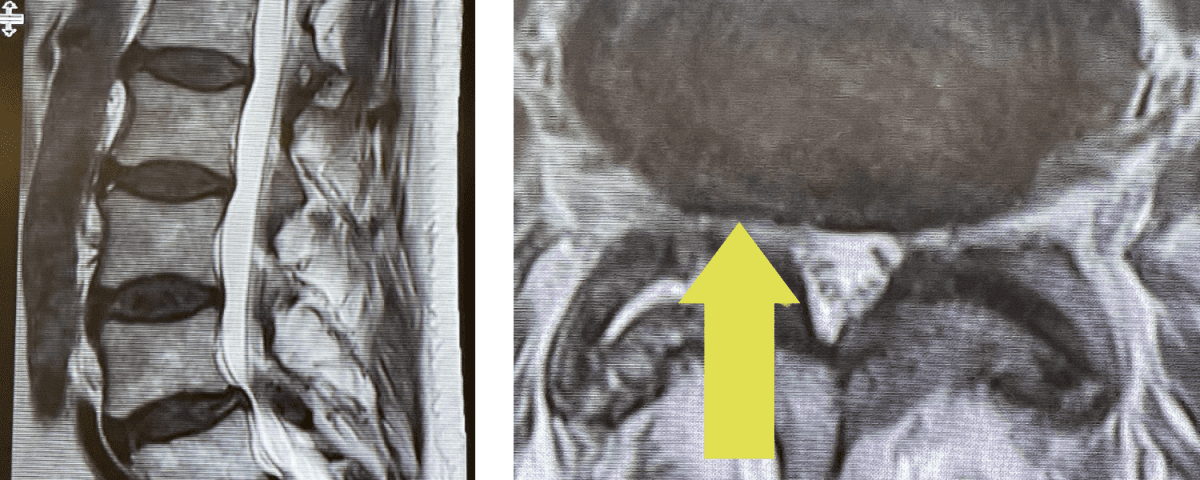

Fig 2: Intraoperative photo showing the thecal sac (arrow)completely decompressed after L3-5 laminectomy. Note the L5 nerve root very well decompressed (asterix)

During the surgery we perform what is called a decompressive laminectomy. Because he had the slip at L4-5 he required a fusion in addition. We elected to use screws with bone graft. People wonder what an actual laminectomy is. A laminectomy is a procedure to remove or “ectomy” the back ring of bone of the spinal segment .You literally bite it away with our special instruments. This bone is called the lamina. You do not need the lamina to live, like an appendix. There are gaps between each lamina segment going up the spine to begin with and there is a tremendous amount of tissue including muscle so one is protected, and it is ok to do this. You need to do the laminectomy to shave away the material that is both hard and soft that is compressing the sac of nerves. Your goal in the surgery is to make the sac nice and round again with a normal diameter. Since in the lumbar spine there is no spinal cord you are dealing with the peripheral nervous system not the central nervous system like the brain and spinal cord. A sac of nerves floating in fluid is a protected system, like a baby in amniotic fluid. At the same time you must not only remove the pressure on the sac, but also you must shave away the pressure on the nerve roots as well, which is called a foraminotomy (Fig 2). The nice thing about a fusion is you can be aggressive in the amount of decompression and joint removal you can do because you are fixing chronic as well as iatrogenic acute instability.